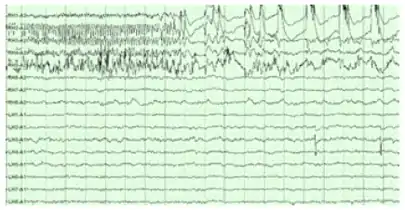

Image 9: An EEG showing epilepsy right-hippocampal seizure onset

Image 10: An EEG showing epilepsy left-hippocampal seizure onset